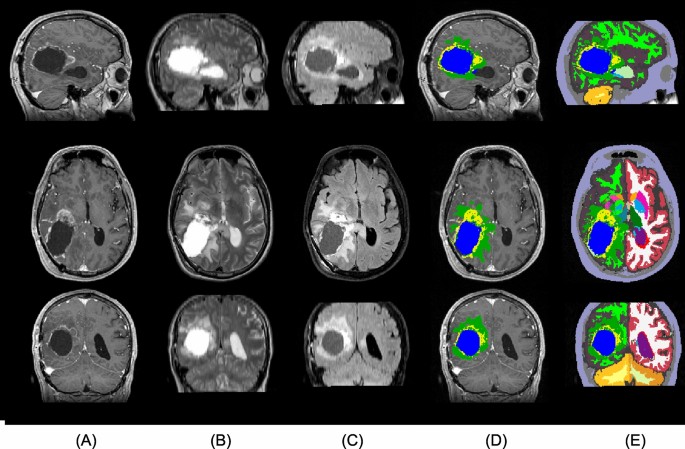

A sample from the Copenhagen (post-operative) dataset. From top to bottom: sagittal, axial, and coronal view. The columns show (A) T1c, (B) T2, (C) FLAIR, and (D,E) the automatic segmentation output. (D) shows the tumor components only, while (E) shows the full segmentation output. The tumor components in (D,E) are edema (green), enhancing core (yellow), and non-enhancing core (blue). Resection cavity is shown in light-green color in the sagittal view of (E).

MR scans were acquired for radiation planning 2–3 weeks post-operatively. The acquired MR modalities included 3D T1 (MPRAGE) post-administration of gadolinium contrast (T1c), T2, and FLAIR (Fig. 4A–C), using a 1.5T Siemens Espree scanner. The T1c scans were acquired using a voxel size of \(0.5 \times 0.5 \times 1.0 \text {~mm}^3\) (matrix size \(384 \times 512 \times 176\)); the FLAIR scans with a voxel size of \(0.45 \times 0.45 \times 3.3 \text {~mm}^3\) (matrix size \(448 \times 512 \times 40\)); and the T2 scans using a voxel size of \(0.3 \times 0.3 \times 3.3 \text {~mm}^3\) (matrix size \(672 \times 768 \times 39\)). As the only form of pre-processing, intra-subject registration and resampling to 1 mm\(^3\) resolution was performed using FLIRT51. Three out of the 146 subjects were excluded as their post-operative MR data was unavailable. Out of the remaining 143 subjects, 11 were missing FLAIR scans and 3 were missing T2. However, our segmentation algorithm is robust with respect to missing modalities, allowing all 143 subjects to be included in the study.